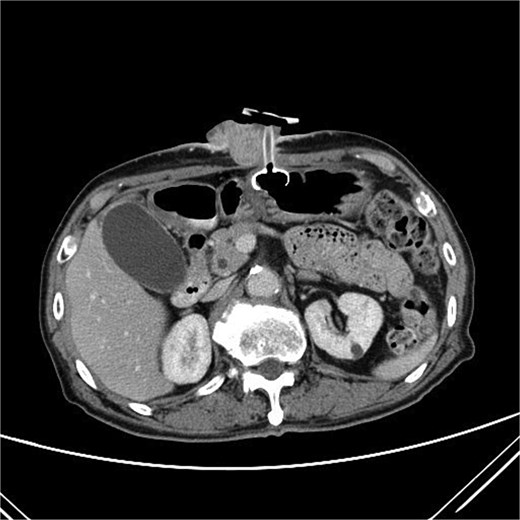

Two months after completing chemoradiotherapy, a large abdominal wall mass measuring 6 x 6 cm with foul-smelling purulent discharge was noted adjacent to the PEG tube site (Fig. 2). Incisional biopsy of the mass was performed and revealed well-differentiated squamous cell carcinoma. According to these clinical and pathological findings, gastrostomy tract metastasis was suspected. A computed tomography (CT) scan of the chest and abdomen showed a 6.2 x 5.6 cm enhancing soft tissue mass in the anterior abdominal wall, centered around the gastrostomy site, extending deep to subcutaneous layer (Fig. 3). There was no evidence of distant metastasis. No mucosal lesion was observed on upper gastrointestinal endoscopy.

A CT scan of the abdomen showed a 6.2 x 5.6 cm enhancing soft tissue mass in the anterior abdominal wall.